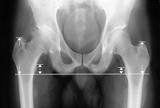

Increased risks of leg length discrepancies and dislocation

You may be surprised that in the age of synthetic medical implants that surgeries result in unequal leg lengths, but it happens. The consequence of unequal leg lengths is a change in the recipient\’s gait and pain while walking. Surgeries also weaken bone and other tissues, leading to a greater incidence of dislocation.